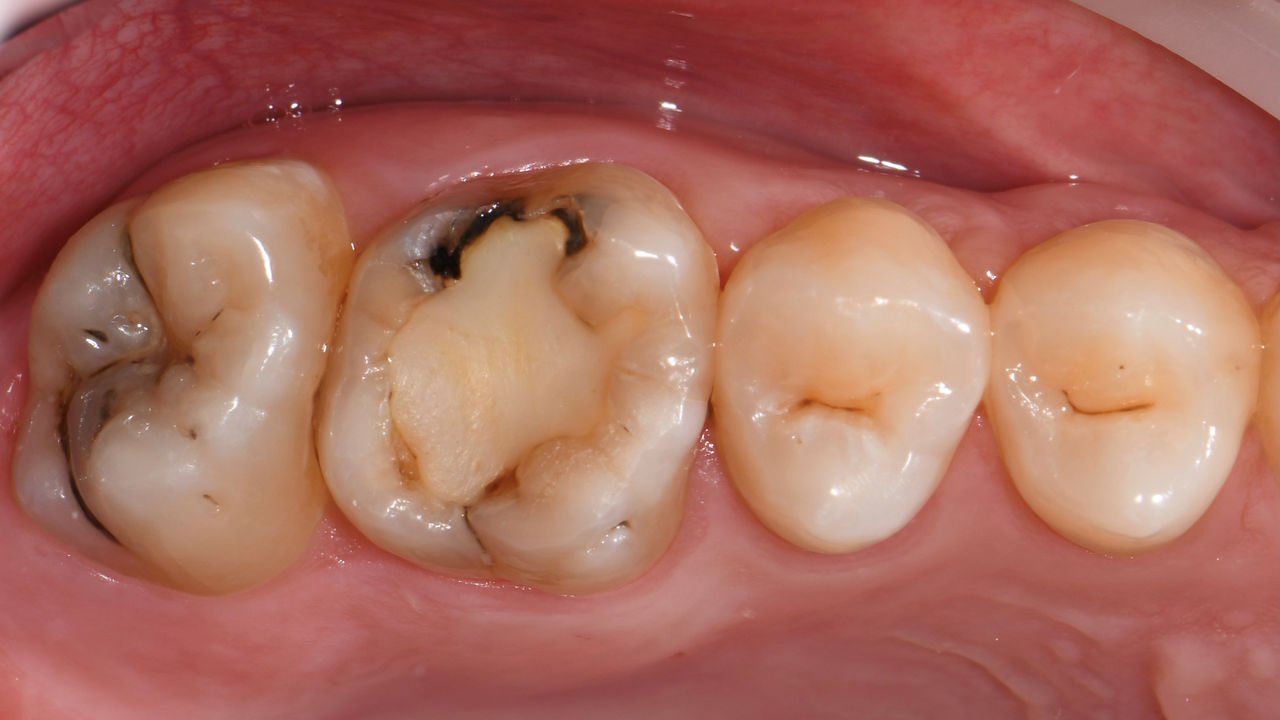

Rehabilitación del cuadrante

Dos coronas CEREC Tessera y dos inlays

En una sola visita de cuatro horas, se realizó la restauración de dos coronas y dos inlays, que tenían 15 años. El paciente quedó muy satisfecho con el muy buen resultado estético.

Antes: Obturaciones insuficientes en el segundo cuadrante. Las restauraciones tenían alrededor de 15 años.

Después: Coronas fabricadas chairside hechas de CEREC Tessera (dientes 26/27). Inlays para los dientes 24 y 25 hechas de bloques de composite.